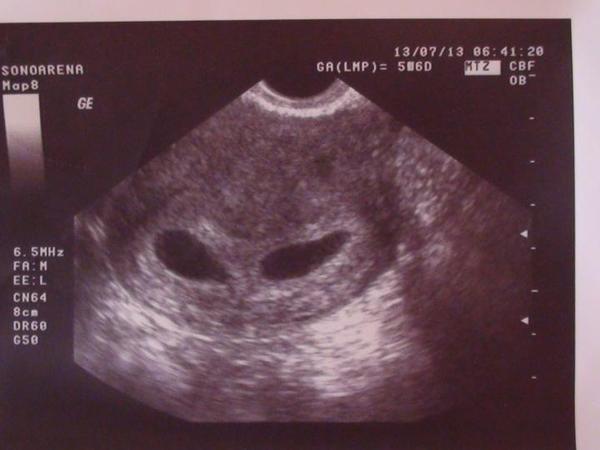

žienky ja som vedla ze som tehu uz tyzden pred ocakavanou mrchou, test ukazoval slabeho ducha...ale doktorke som bola objednana az 13.7. doma mam uz uz trojrocneho sibala tak som aj bola rada ze bude este jedno do partie k nemu ale u doky som zažila sok ktorý som necakala namiesto jednoho budu babatka dve!!!

@gitusa23 ja som bola 5t+4 a bolo uz vidno aj srdiecko 🙂. ale tiez ma este sestricka predtym upozornovala, ze sa nemam zlaknut, ak nebude nic vidno 🙂

@gitusa23 ja som bola 5+2tt a videli sme len prazdny vacok, piatok ideme na kontrolu tak dufam ze bude i srdiecko.

ahojte baby, mne vychadza termin koniec februara, ale mozno to bude aj zaciatok marca 2014 kvoli posunutej ovulke, tak sa k vam nesmelo pridavam ;) u doktorky som bola 6tt+5 a bilo uz srdiecko 🙂

@dadulajda a v ktorom si tyzdni? mne dala doktorka foto 6tt+5 😉

@suzi1617 mala by som byt v 7.ale to podla kramov.neviem ci aj naozaj..